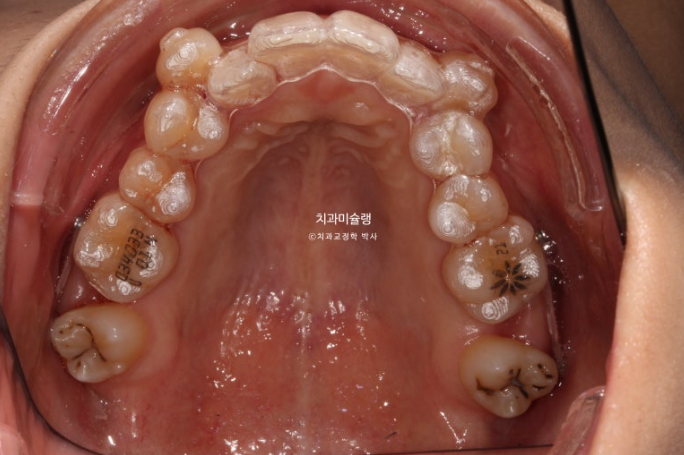

24.09

인비절라인 비발치 교정으로 덧니는 대부분 해소되었으나 중심선 불일치가 남았고

큰어금니 교합은 아직 엉성합니다.

미진한 부분을 개선하고자 인비절라인 비발치 재제작에 들어갔고 24년 11월부터 25년 4월까지 18개 추가장치를 모두 낀 후 모습입니다.

25.04

중심선 불일치가 아직 약간 남아있습니다.

삐뚤했던 치아들에서 블랙트라이앵글이 눈에 띕니다.

치간삭제를 처방하여 블랙트라이앵글의 추가적인 개선, 어금니 교합 개선, 중심선 개선을 목표로 두번째 추가장치 제작에 들어갑니다.

상악 제2대구치 발치공간을 이용하여 송곳니 덧니를 배열했습니다.

사랑니는 발치한 두 번째 큰어금니 자리를 잘 채워주고 있습니다.